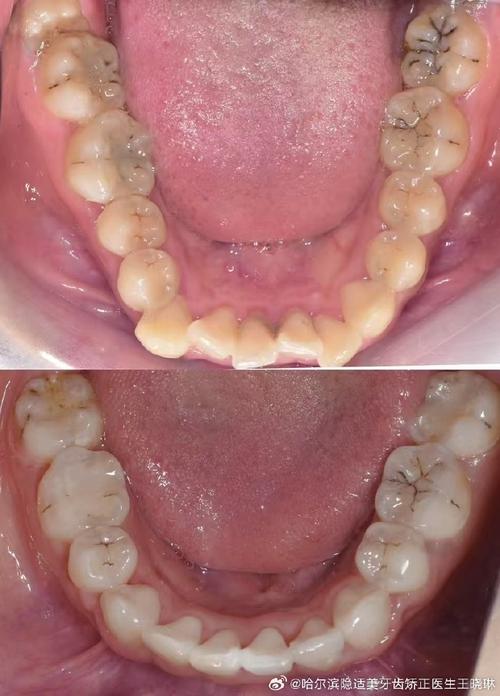

这是最常见的拔牙原因,如果牙齿过多,而牙弓空间不足,牙齿就会相互挤压、扭转、重叠,甚至部分牙齿完全被挤出牙弓外,此时拔除部分牙齿(通常为前磨牙),可以为其他牙齿提供移动空间,使其排列整齐,不仅改善美观,还能避免清洁困难导致的龋齿、牙周病等问题。

拔牙后,医生会根据患者情况选择矫治器类型(如传统金属托槽、陶瓷托槽、隐形牙套等),通过施加持续、轻柔的力,牙齿会在牙槽骨中缓慢移动:拔牙间隙两侧的牙齿会向中间靠拢,前牙会向后移动关闭间隙,后牙可能前移调整咬合关系,整个移动过程通常需要1.5-2年,期间每4-6周复诊一次,调整矫治力。